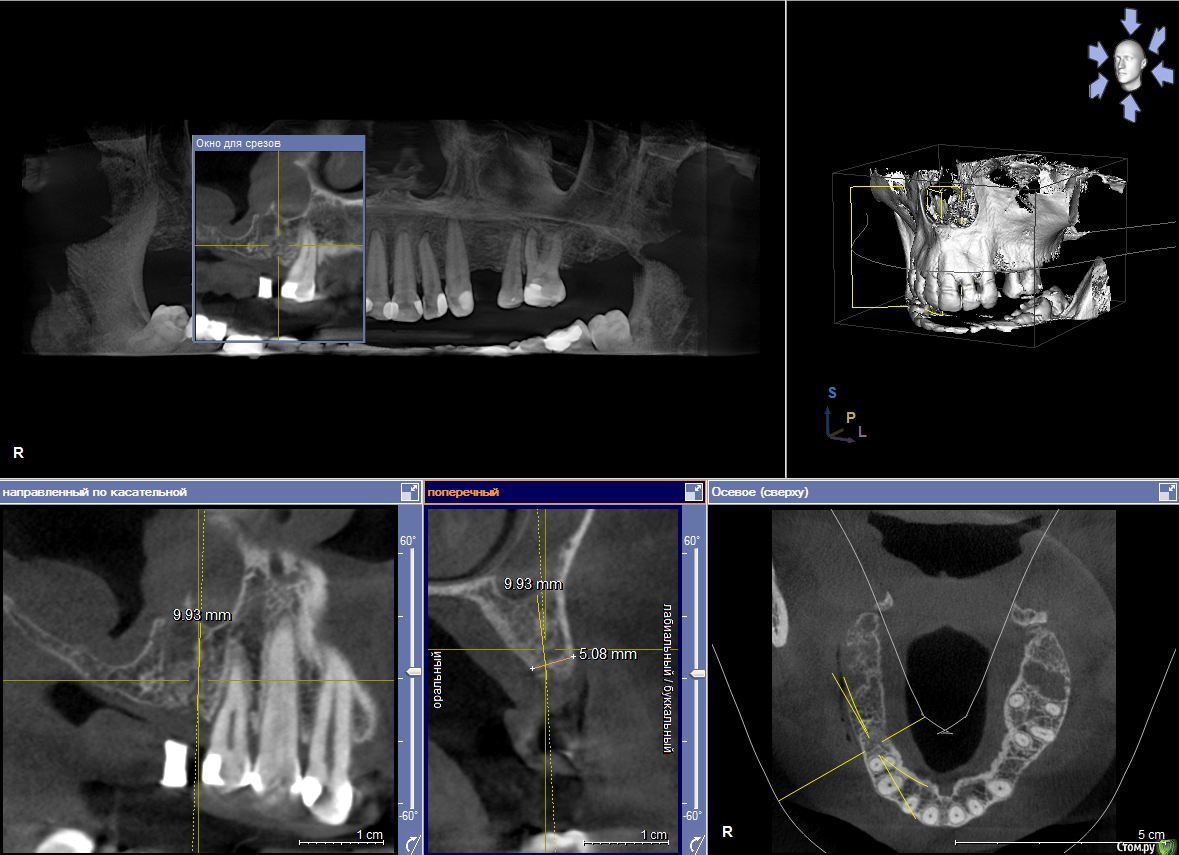

1) имплантация в позиции 15,17 з с закрытым синусом и незначительной НКР

2) коррекция слизистой в области 1-го сегм

3) имплантация с ССТ в позиции 24 з ( после дистализации 25,26 з), в области 27 з на момент  операции был гнойный синусит, отложили